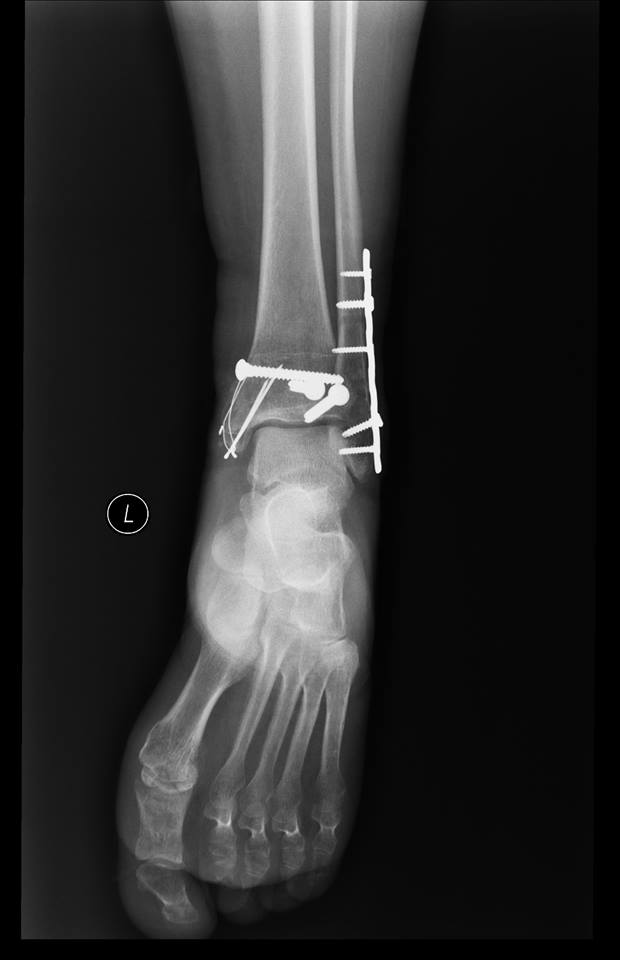

Były wzloty i upadki, z których starała się wszelkimi sposobami podnieść. Dawała jeszcze radę. Jednak w lutym 2016 r. doznała poważnego urazu nogi w wyniku wypadku. Przesiadła się na wózek inwalidzki. Dwie operacje i walka o nogę, żeby jej nie amputowali.